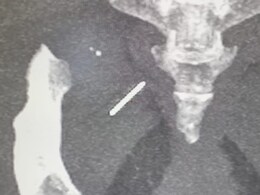

Needle Embedded In Hip: सर गंगा राम अस्पताल में, रंभा की सर्जरी से पहले एक्स-रे और सीटी स्कैन के साथ इमेजिंग की गई.